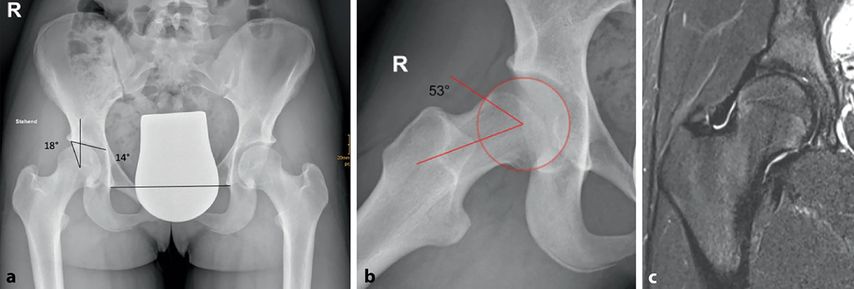

Abb. 1: 14-jährige aktive Balletttänzerin mit Schmerzen bei starker Abduktion und Außenrotation. Im Projektionsröntgen ap (a) zeigt sich eine Grenzdysplasie (LCE-Winkel 18°, Tragflächenwinkel 14°), in der Dunn-View (b) ein verminderter femoraler Offset mit einem Alpha-Winkel von 53,4°. Die MRT (c) zeigt ein geringgradiges Knochenmarködem am Kopf-Schenkelhals-Übergang als Zeichen des FAI (aus Chiari et al. 2022)5

Die Beckenübersichtsaufnahme im Liegen oder Stehen und die axiale Aufnahme des Hüftgelenks stellen die radiologische Basisdiagnostik dar. Die Cam-Morphologie wird am besten in der Dunn-Aufnahme dargestellt. Die Quantifizierung der Cam-Morphologie erfolgt durch Messung des Alpha-Winkels nach Nötzli auf Röntgenbildern (Abb.2b,d).16 Der Abrutschwinkel einer ECF wird in der axialen Lauenstein-Aufnahme gemessen.

Die Magnetresonanztomografie zählt mittlerweile ebenfalls zum Goldstandard. Das Ausmaß und die Lokalisation einer Cam-Morphologie werden durch radiäre Rekonstruktion nach der Ziffernblattmethode beurteilt. Knochenmarksödeme im Bereich der Kontaktzonen können indirekte Zeichen eines FAIS sein. Weiters werden Labrum und Knorpel beurteilt. Die MR-Arthrografie (optional mit Traktion) ist die beste Möglichkeit, die Knorpeloberfläche und Labrumläsionen zu beurteilen, ist jedoch aufgrund der Invasivität bei Kindern und Jugendlichen zurückhaltender einzusetzen. In diversen Studien wurde nachgewiesen, dass sowohl bei primären Cam-Morphologien als auch bei Zustand nach ECF Knorpel- und Labrumschäden auftreten. Das Ausmaß der Schäden ist umso größer, je höher der Alpha-Winkel ist.12,17,21 Die Beurteilung von Sekundärschäden an Knorpel und Labrum ist für die Operationsindikation und -planung von Bedeutung, damit rechtzeitig interveniert werden kann.2 Ergänzend wird eine Analyse der Torsionsverhältnisse, optimalerweise mit MRT, empfohlen.